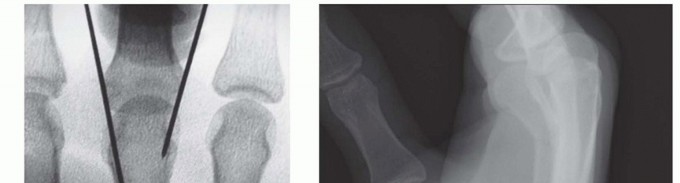

TRANSVERSE PINNING

TECH FIG 2 • A. Angled metacarpal neck fracture. B. Incision at the ulnar base of the fifth metacarpal, exposing the insertion of the extensor carpi ulnaris (ECU) on the base of the metacarpal. Incision located on ulnar aspect of metacarpal to minimize irritation of the extensor tendons. C. Unicortical tunnel at the base of the metacarpal. D. Sample of prebent pin. Tip is angled to facilitate passage through the shaft. E. In metacarpal neck fractures or those at risk of shortening, it is important to bring the pins to the subchondral bone of the metacarpal head but not violate the head.

TECH FIG 3 • A. Second metacarpal fracture with an intact adjacent metacarpal and a narrow medullary canal. B. Fixation using one proximal pin to secure the shaft and two distal pins to secure the distal fragment. C,D. Fracture where the narrow medullary space made it difficult to pass a second wire through the canal. Supplemental fixation achieved through a transverse pin on the distal fragment. The fracture is anatomically reduced through closed means.The proximal fragment is first stabilized by pinning it to the adjacent intact metacarpal.Use the nick and spread technique while placing the wires to minimize the risk of iatrogenic cutaneous nerve injury.Keep pressure between the adjacent metacarpals to prevent convergence between the metacarpals as the wire is advanced.Be mindful of the arch-like arrangement of the metacarpals.The distal fragment is stabilized by placing two wires through the distal fragment into the adjacent intact metacarpal (TECH FIG 3B).The hand is immobilized in a forearm-based splint with the MP joints flexed 70 to 90 degrees while the pins are in place. The pins are kept for 3 to 4 weeks. The IP joints are left free to move.The pins are removed at 3 to 4 weeks, and the hand is placed in a removable splint for an additional 2 weeks.Alternatively, transverse pins can be used to augment other forms of fixation or control rotation (TECH FIG 3C,D).1. Open Reduction and Plate/Screw Stabilization of Metacarpal Fractures